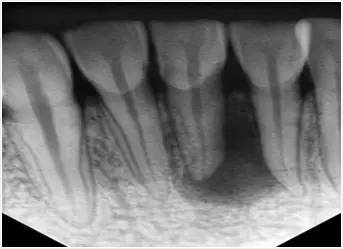

1、术前拍摄X线片

在根管治疗过程中,在根管治疗术前拍X线片,以帮助诊断,了解髓室的位置和根管数目及形态,测量根管工作长度及日后随访和评价疗效提供对比的依据。